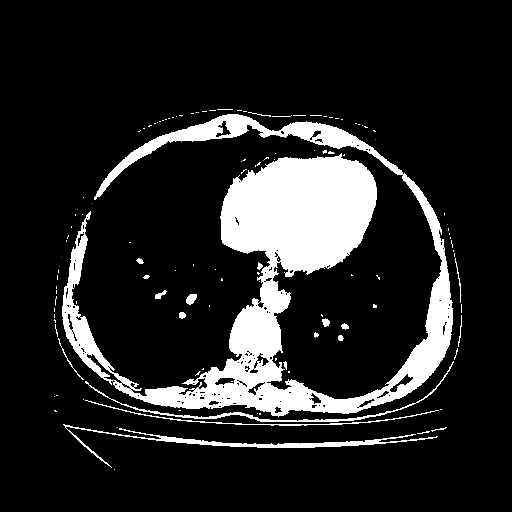

Image Grid

4Γ—3 grid: Rows show different image types (Original NATIVE, Reconstructed NATIVE, Original VENOUS, Generated VENOUS), Columns show windowing techniques (No Window, Lung Window, Mediastinum Window)

Original VENOUS CT scan

Full window (WL 1023.5, WW 4095 β†’ Low βˆ’1024, High +3071)

Actual HU range: [-1024.0, 3071.0]